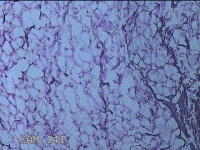

外阴部包块

性别

女

年龄

37岁

临床诊断

皮脂腺囊肿

一般病史

外阴部起包块一月余。

标本名称

大体所见

灰白暗红色包块2.3x1.8x0.8cm一个,表面糜烂,切开包块呈实性,切面灰白淡黄色,质软。

图1

有那么点像脂肪瘤。